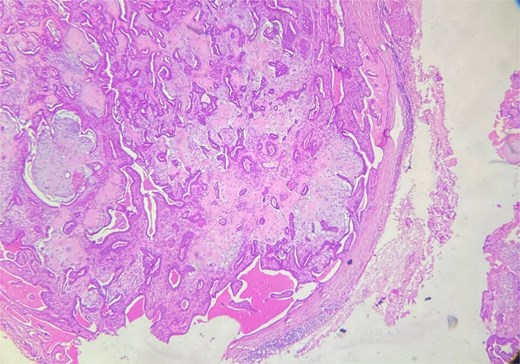

A 53-year-old Moroccan man, with no significant medical history, presented with a cheek swelling evolving over 6 months without associated symptoms. Clinical examination revealed a 1.7 cm cystic-like swelling in the cheek, suggestive of a ruptured epidermoid cyst. It was mobile and skin-colored, without inflammatory signs. Lymph nodes and salivary glands were normal. An excisional biopsy of the mass was performed. Macroscopically, it was a 1.7 cm beige, friable to firm, rounded nodule. Microscopic examination showed a well-circumscribed benign tumor proliferation composed of cysts, tubules, and ducts (Fig. 2), lined by a bilayered epithelium. The cells exhibited no nuclear atypia (Fig. 3). The fibromyxoid and chondroid stroma allowed for diagnosis without additional techniques. There was no perineural invasion or vascular emboli, and surgical margins were clear. Postoperative recovery was uneventful, and no further follow-up or additional examinations were necessary.

Benign tumor proliferation composed of cysts, tubules, and ducts.